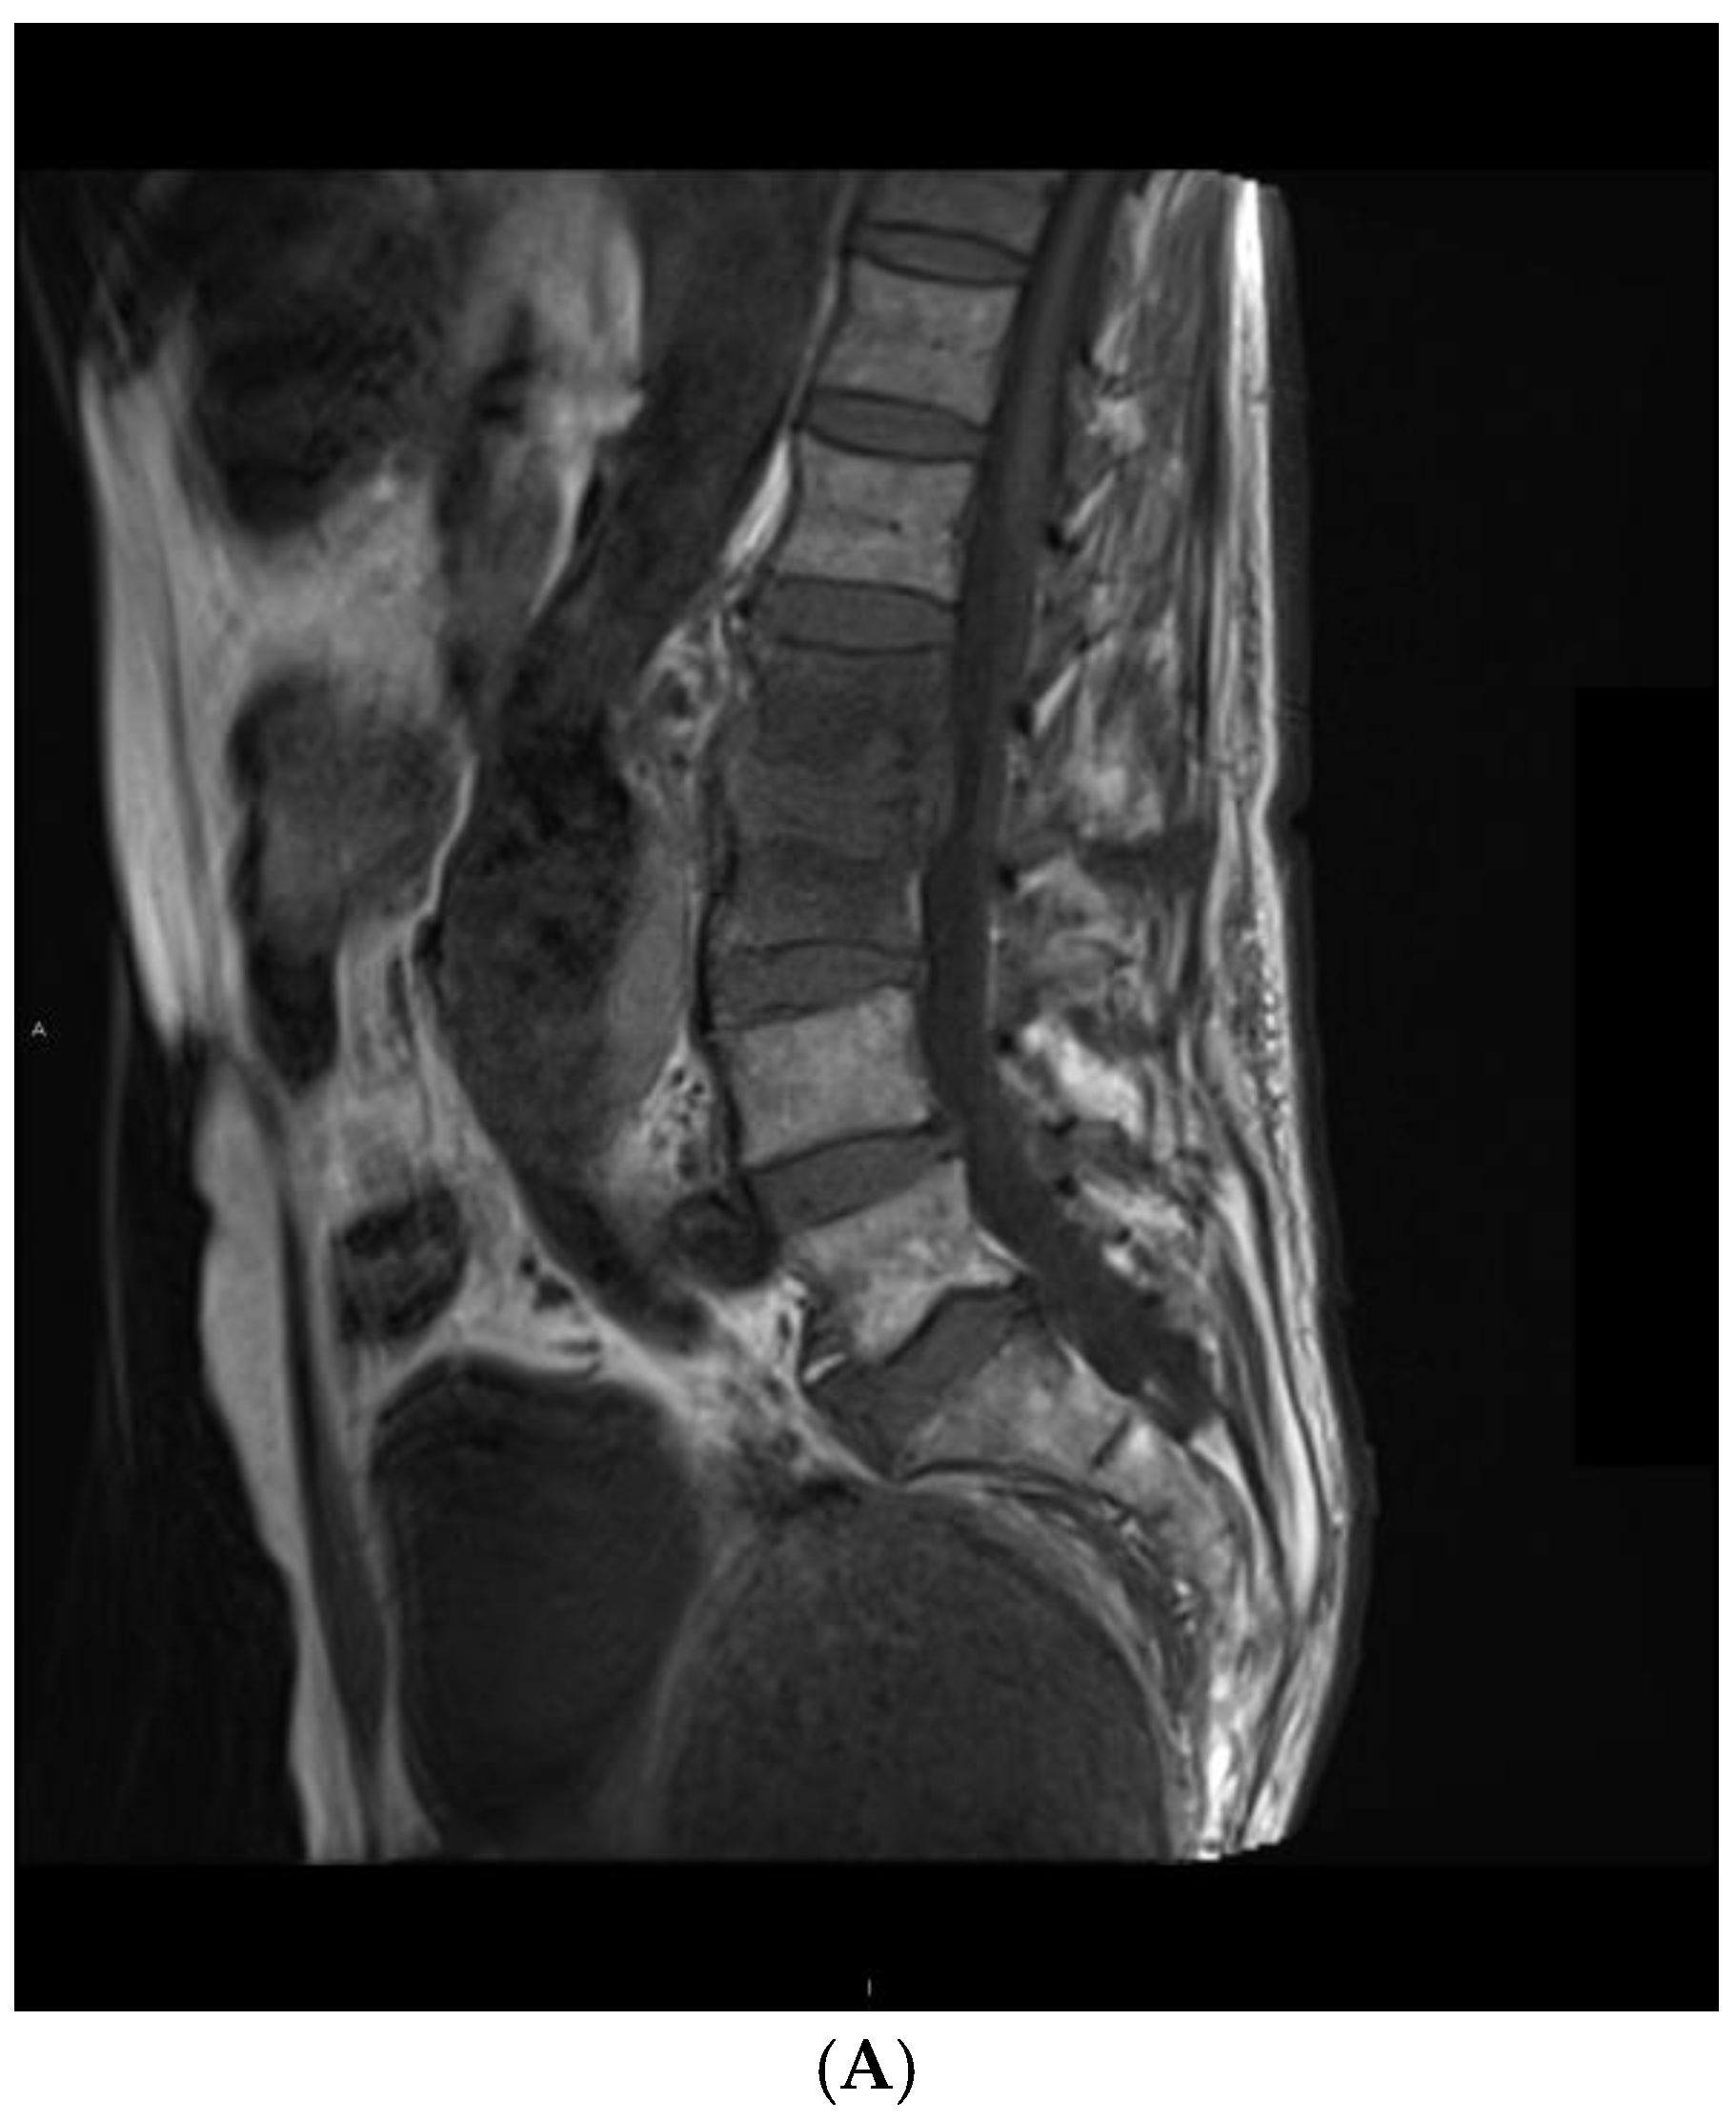

Figure 1. An example of pyogenic spondylodiscitis imaging features in a 68-year-old patient. Images in (A) T1 sagittal, (B) T2 TIRM sagittal, and (C) T1 sagittal with contrast sequences. There is inflammatory involvement of Th11 and Th12 vertebral bodies and an abscess in the Th11–Th12 disc.

The distribution of vertebral body signal changes on T1-weighted images was not significantly different between groups (p = 0.214). However, a difference was observed on T2 TIRM images (p = 0.001) (Table 3). The majority of pyogenic bacterial infections had a hyperintense signal (89%), whereas a heterogeneous signal characterized tuberculosis (69%). Changes in the signal of intervertebral discs had a similar distribution on T1-weighted images (p = 0.229) and T2 TIRM images (p = 0.245). Distributions of the range of signal changes in the vertebral bodies did not differ significantly between T1-weighted and T2 TIRM images (p = 0.308). An example of the features of a pyogenic infection is shown in Figure 1.

Tuberculosis was associated with more intense destruction of vertebral bodies. Most patients in this group (75%) had advanced destruction of more than 50% in height, while 56% of patients with pyogenic bacteria had a loss of between 25% and 50% in height (p = 0.016). The condition of the border plates did not differ between the groups (p = 0.152); all patients had erosions or destruction. There were also no differences in the level of destruction of the intervertebral disc (p = 0.560). The fluid signal within the intervertebral disc was observed in 12 patients with pyogenic bacterial infection and in 6 patients with tuberculous infection (p = 0.448). An example of the features of a pyogenic infection is shown in Figure 2.